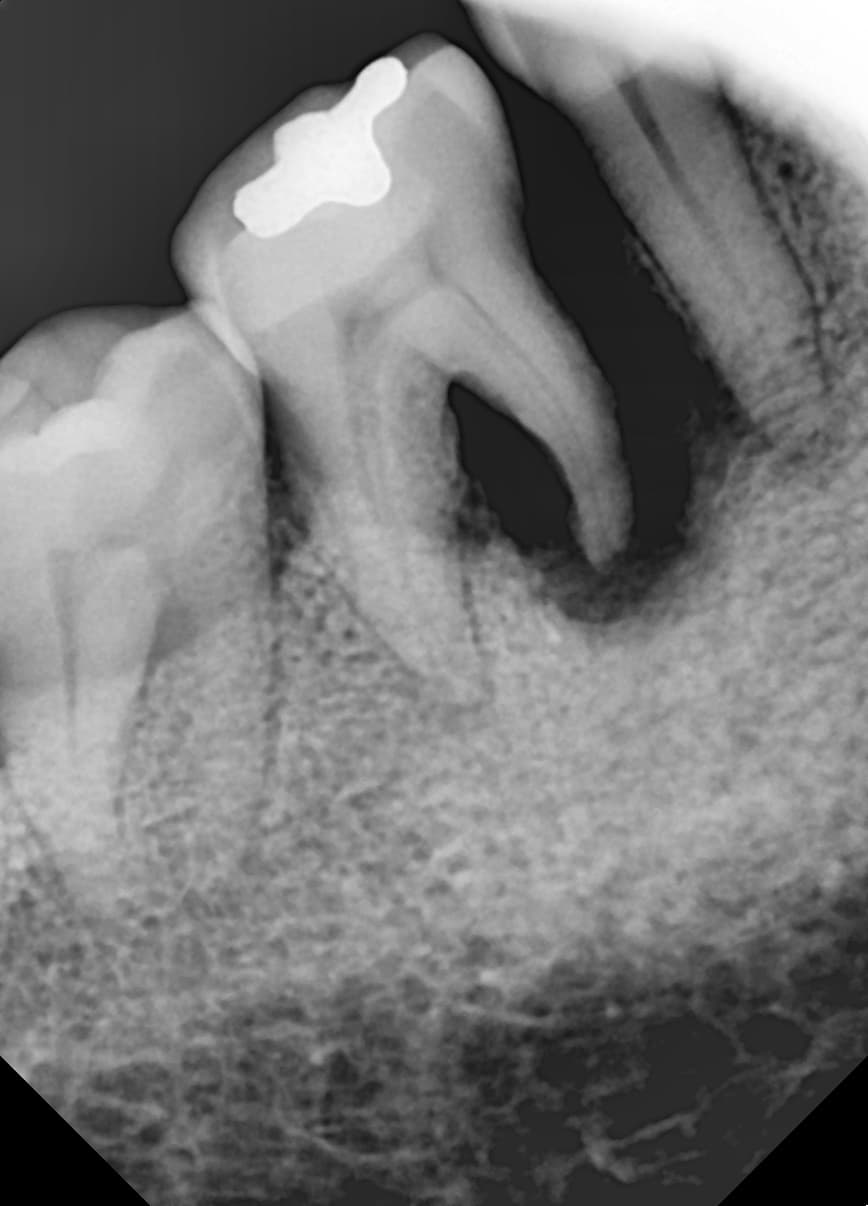

"骨质严重流失

牙龈治疗后骨质得到恢复"

Before

After

严重牙龈病导致骨质大量流失的状态

牙龈治疗和骨移植再生后植入种植牙